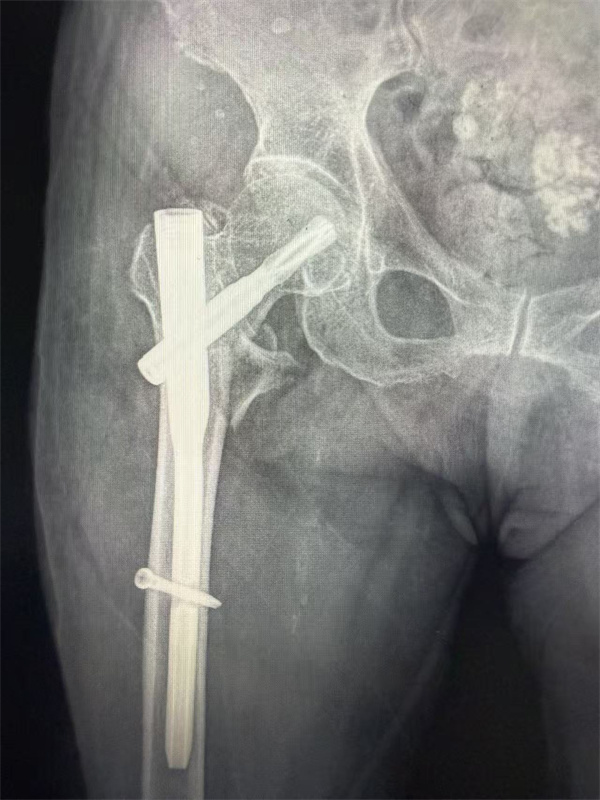

专家团队没有轻易放弃,温鑫柱选择微创髓内钉术式,该手术可以在1小时内完成,最大程度减少手术创伤及出血;姜丽考虑老人服用抗凝药物无法腰麻,且高龄患者尽量避免气管插管后,决定采用外周神经阻滞+镇静的麻醉方式,最大限度的减少麻醉药物对中枢系统的影响;王轩则对围手术期的心脏管理做了全面的指导及应急预案。同时,功能科、检验科、放射科等相关科室也积极配合应对,血库紧急备血,保证手术供血;放射科、功能科加急进行术前相关检查,为手术提供精准依据。不同于传统诊疗模式,团队不仅通过CT三维重建精准判断骨折类型,还对患者心肺功能、血压控制、营养状况等进行全面排查,在与患者家属进行全面的沟通后,最终制定了“闭合复位小切口髓内钉内固定术+精准麻醉+ERAS全程管理”的个性化方案,并决定于次日进行手术治疗。

手术当日,姜丽带领的麻醉团队摒弃传统全麻方案,采用“髂筋膜阻滞及股外侧皮神经阻滞+中度镇静”的精准麻醉方式,最大限度减少对老人心肺功能的影响。术中持续监测指标,确保生命体征稳定。B超引导(可视化)的神经阻滞,精准定位、精准给药,不仅使副作用减少,更能让镇痛的时间延长到术后。手术由温鑫柱和骨科李观清医生共同完成,仅用时40分钟便完成骨折复位与固定,术中出血不足50ml,创伤小、恢复快的优势尽显。